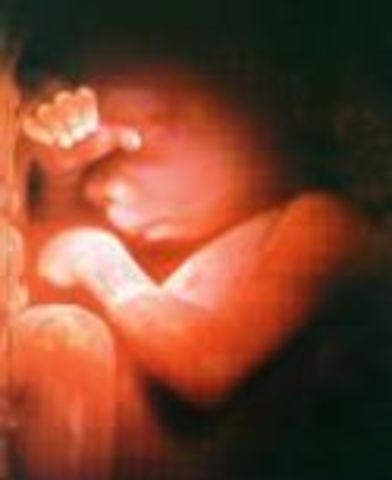

• Week 28

Week 28

The baby is now entering REM sleep and the eyelids can open now. If this baby was born prematurely they have a 90% chance of living.